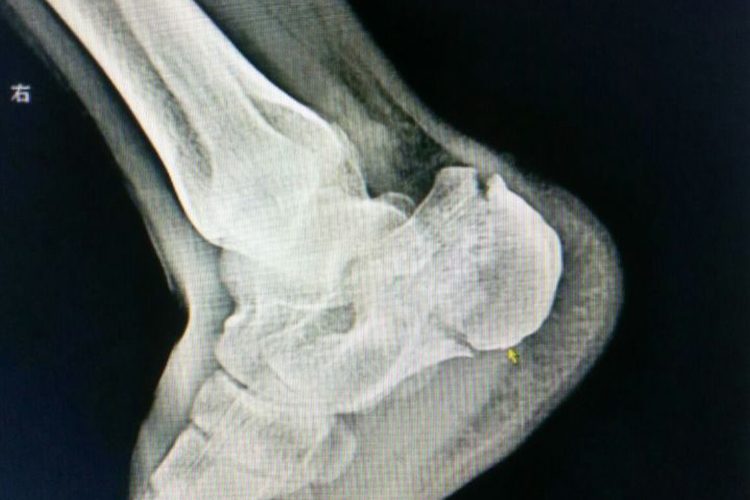

跟骨粉碎性骨折是足部比较常见的损伤,表现为外伤后出现足跟部疼痛、肿胀,踝后沟变浅、皮下瘀斑,足底扁平及局部畸形,不能行走。检查足跟部有局限性压痛,叩击痛明显,跟骨横径较健侧增宽,足底变长。踝关节正位、侧位和跟骨轴位X线平片,可明确骨折的类型、移位程度,多提示跟骨骨质破裂成三块以上。